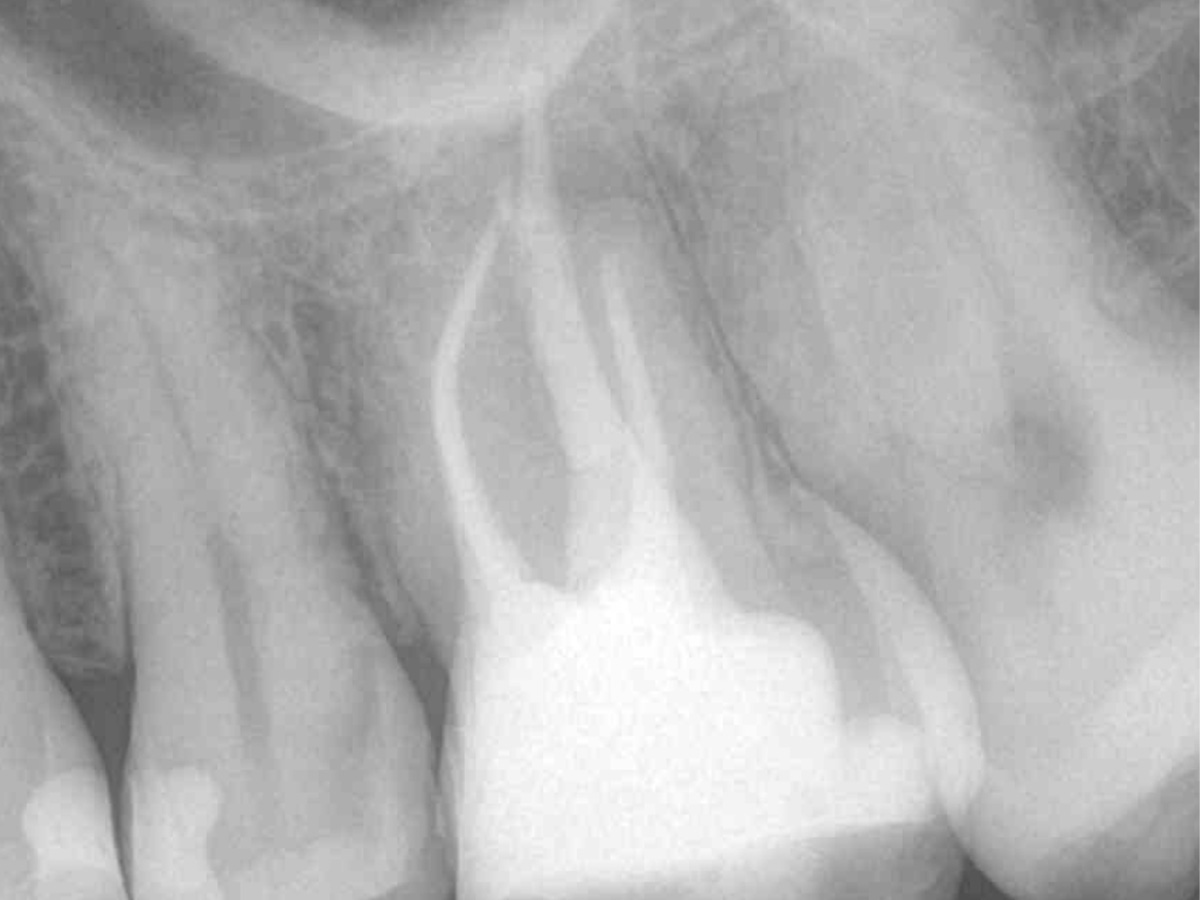

Obturation nach einer erfolgreichen Revision der insuffizienten Wurzelkanalfüllung mit einer symptomatischen apikalen Parodontitis

Der Patient stellte sich mit Aufbissschmerzen vor, wobei die klinische und röntgenologische Untersuchung eine symptomatische apikale Parodontitis an einem bereits wurzelkanalbehandelten Zahn 26 ergab. Die DVT-Aufnahme deutete auf einen unbehandelten zusätzlichen Kanal in der mesio-bukkalen Wurzel hin. Die Darstellung und Behandlung des mb2s sowie die Revision der bereits behandelten Kanäle erfolgte mit dem XP-endo® Rise Shaper bei einer hohen Umdrehungszahl von 2.500rpm.

Die Arbeitslängen der Kanäle wurden mittels elektrometrischer Messung bestimmt und die Kanäle aufbereitet. Alle Kanäle außer dem palatinalen wurden bakteriendicht mit einer Sealer-basierten Wurzelfülltechnik (Guttapercha und TotalFill® BC Sealer) verschlossen.

Für den ovalen Querschnitt der palatinalen Wurzel wurde eine warm-vertikale Technik angewendet. Dazu wurde der Guttapercha Hauptstift mit dem B&L Alpha und einem Hitzeplugger (55/.08) in der Tiefe abgetrennt und kondensiert.

Mit dem B&L Beta wurde der restliche Kanal nach der Backfill-Technik schrittweise mit erwärmter Guttapercha aufgefüllt. Die abschließenden Röntgenaufnahmen zeigen das Ergebnis, das mit den kabellosen Systemen präzise und effizient umgesetzt werden konnte.

Abbildung 3

DVT sagittal

Wurzelfüllung 26 exzentrisch

Abbildung 7

Wurzelfüllung 26 orthoadial